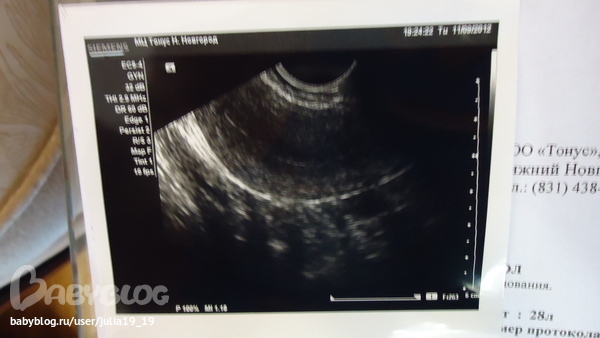

А это на 14 д.ц.

Подскажите, какие еще обследования нужно пройти, чтоб исключить или подтвердить этот полип? т.к. меня скорее всего направят на выскабливание... а если это не полип, не хочется лишний раз трогать эндометрий при выскабливании... потому что я планирую беременность... Пожалуйста, Аркадий Владимирович, подскажите как мне быть?